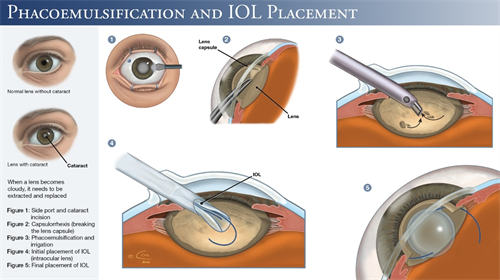

白内障手术是一种非常常见且安心的眼科手术,通常采用超声乳化技术将模糊的晶状体取出,然后植入人工晶状体以改善眼部视力。